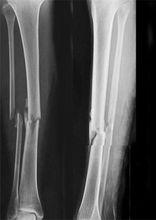

長骨骨折發生於四肢長骨,由於外傷或疾病所引起的骨結構的完整性或連續性受到破壞,以疼痛、腫脹、功能障礙、畸形及可捫及骨擦音、異常活動等為主要臨床表現的疾病。

1、創傷所致長骨骨折主要有2個原因:1、直接暴力:為暴力直接作用於骨骼某一部位而致該部骨折,常伴有不同程度軟組織破壞,如車禍中,車輪碾壓所致的股骨幹骨折;(2)間接暴力作用時通過縱向傳導、扭轉或槓桿作使遠離外力部位發生骨折,如高出墜落時,高能量軸向傳導所致的脛腓骨骨折。